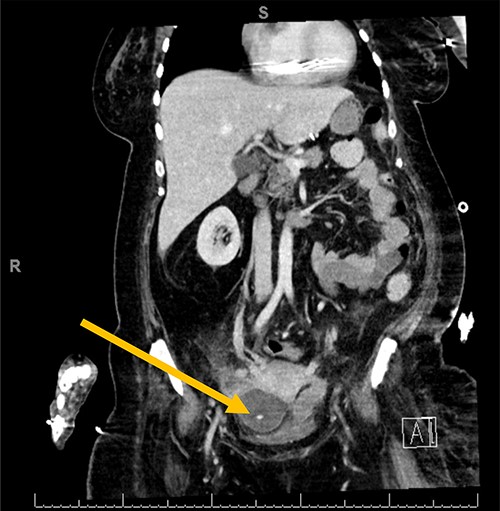

The patient is a 54-year-old woman with locked-in syndrome, which is complete paralysis of all voluntary muscles excluding those that control ocular movements, secondary to Guillain–Barré Syndrome (GBS) who had a laparoscopic adjustable gastric band placed in 2008. A few months prior to her presentation to the emergency department, the subcutaneous port of the band was removed by her care team without consultation from a surgery team, as the skin site appeared to be infected. Of note, the tubing was left in situ. The patient presented to the emergency department with generalized abdominal discomfort for 1 week associated with fevers noted by her caregivers. Upon admission, she was resuscitated and treated with broad-spectrum intravenous antibiotics. A computerized tomography scan of the abdomen and pelvis revealed a pelvic abscess around the tip of the gastric band tubing (Fig. 1). She did not improve after 5 days of medical management; therefore, the patient was consented for surgical removal of the gastric band and tubing.